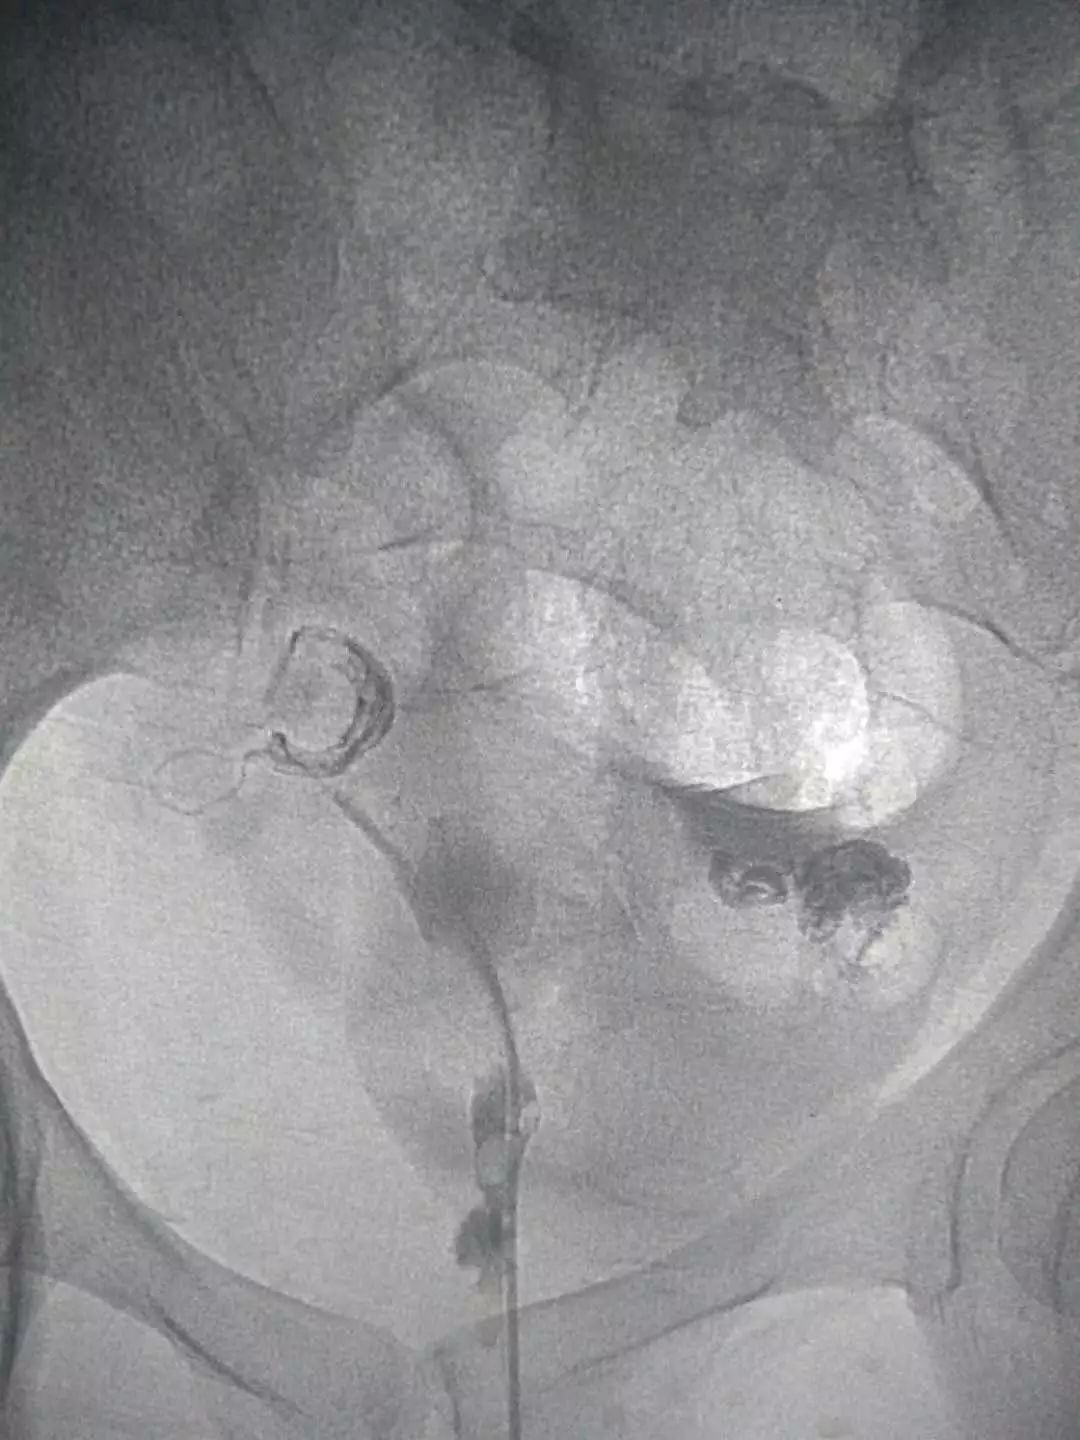

这是我院介入科开展的其中一例输卵管再通术:

患者四年前由于一次流产,之后一直不孕,在当地行子宫输卵管造影发现右侧有输卵管狭窄,当时采取保守治疗。四年来一直未孕。经过沟通,她在我院接受了输卵管介入复通术治疗。

造影视:双侧输卵管近段狭窄,右侧伞端通而不畅,左侧输卵管管壁不规则,通而不畅。

依次开通右侧输卵管+灌注药物,左侧输卵管+灌注药物,造影,显示左侧输卵管完全通畅。